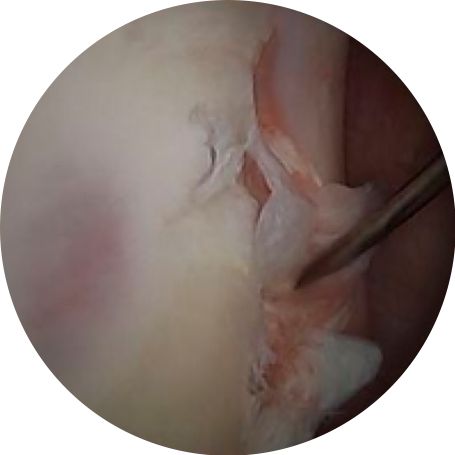

Arthroscopic imaging of tearing along the intra-articular portion of the biceps long head tendon.

Arthroscopic imaging of tearing along the superior labrum, also termed a "SLAP" tear.